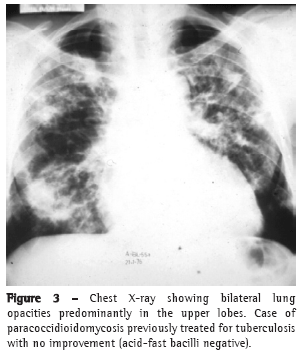

In most cases, the clinical complaints, the physical examination data, and the radiological alterations presented by these patients did not allow a clear distinction to be made between the two diseases in most cases (Figures 2-4).

Pulmonary alterations are typically bilateral, predominantly in the middle lobes and spinal cord regions.(16,17)

In contrast, TB affects males and females of all ages, the majority of whom are symptomatic and present abnormal physical examination findings, as well as radiological alterations, which can also be bilateral but are typically most pronounced in the superior and posterior segments.